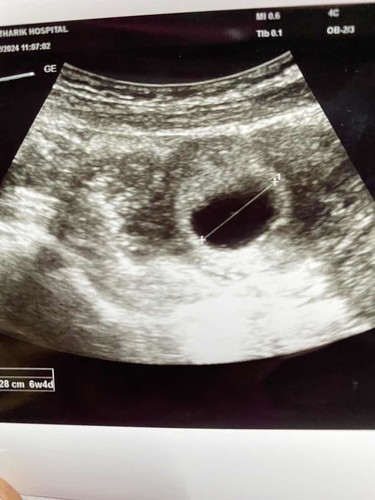

แม่ๆคะคือไปซาวตอน6วีค4วันเจอแบบนี้แต่ยังไม่ได้ยินเสียงหัวใจถือว่าปกติมั้ยคะซาวทางหน้าท้องคะคุณหมอนัดอีกที7มีนาคะ